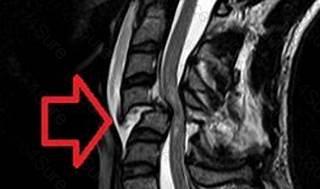

A patient with a spinal cord injury at T7 tells the nurse that they now...

A patient with a spinal cord injury at T7 tells the nurse that they now have a pounding headache. The nurse should

check for bladder distension.